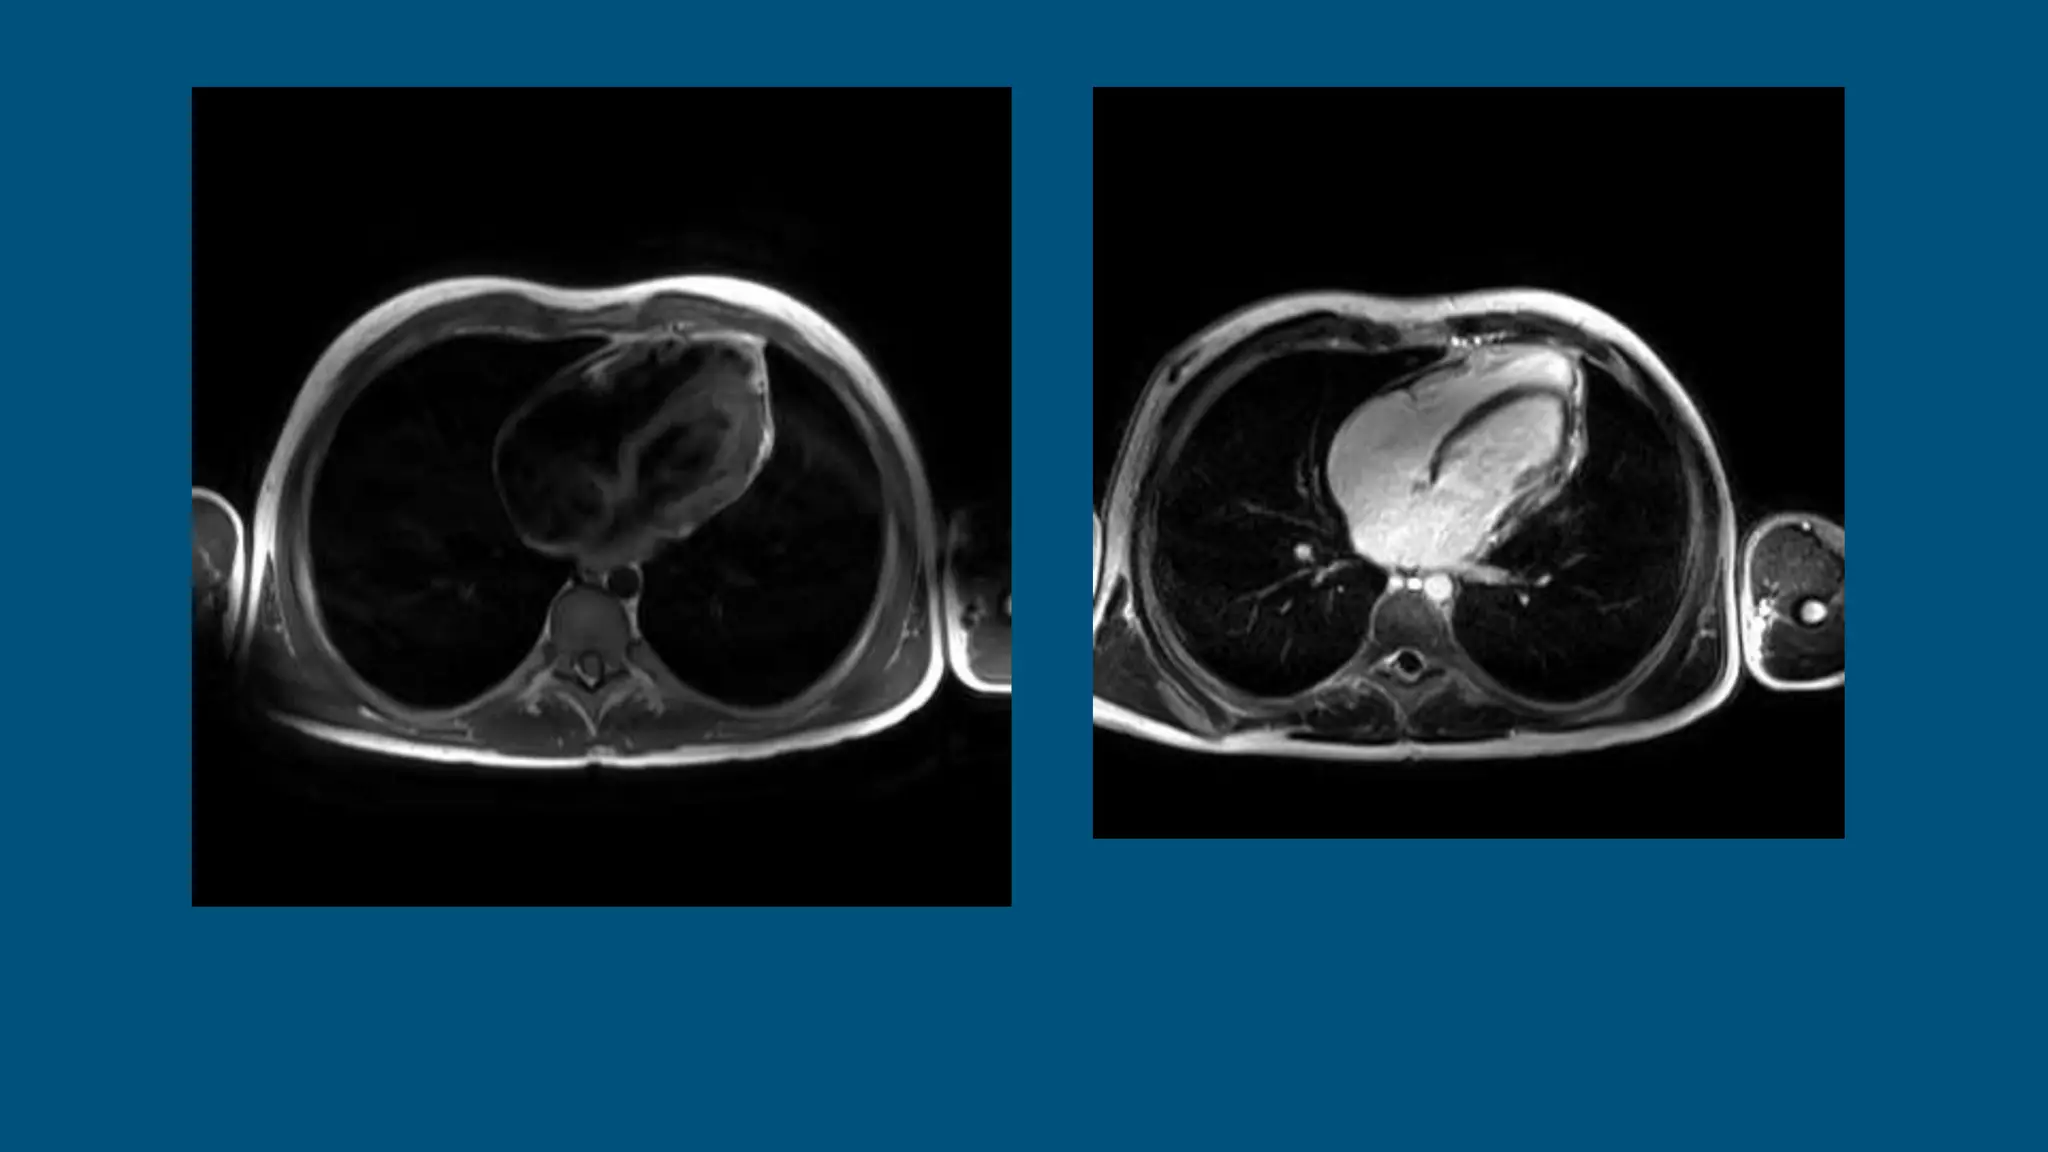

The patient is an 18-year-old male who presented with fever, abdominal pain, and dark urine 6 weeks ago and was diagnosed with mononucleosis. Further imaging found incidental pericardial calcifications. The patient has since developed dyspnea and palpitations. On exam, jugular vein distention and hepatosplenomegaly were present, as well as a precordial knock. Imaging and testing showed calcific constriction of the pericardium consistent with calcific pericarditis.